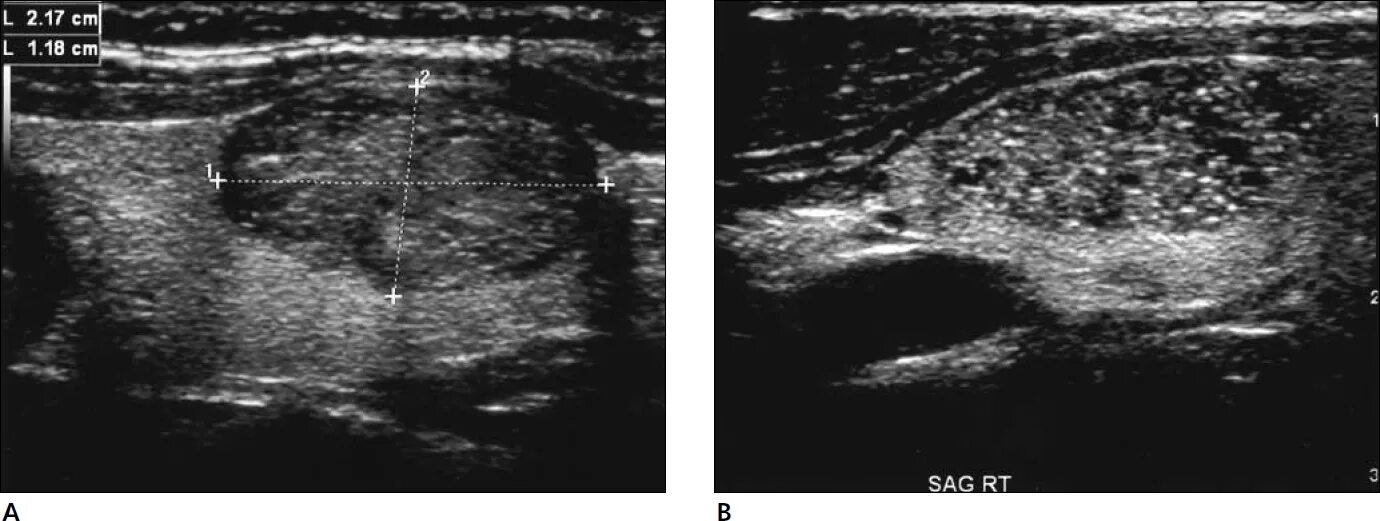

Диффузные узлы